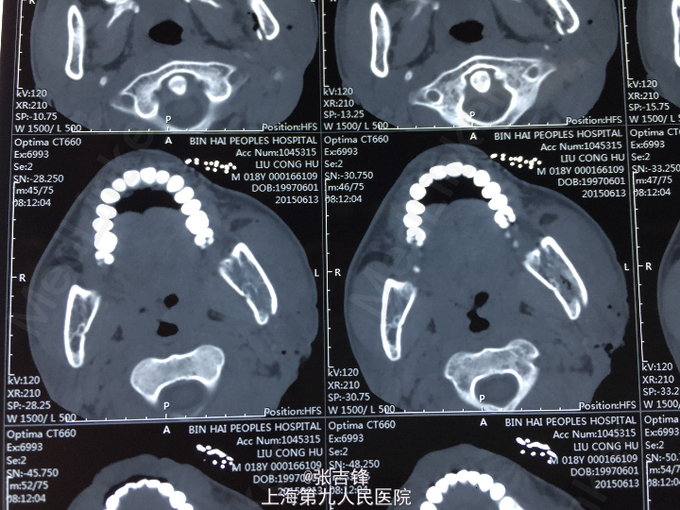

神志清楚,左面颊部长约10cm开放性创口,深达骨面,活跃性出血,可见下颌升支横行骨折,异常动度,腮腺破损,腮腺导管断裂,张口度2cm,咬合关系尚可,口角无偏斜,左侧鼻唇沟变浅。 CT:左侧下颌升支骨折

诊断:左侧面颊部软组织刀砍伤,下颌升支骨折,腮腺腺体损伤导管断裂,面神经下颊支断裂 处理:急诊止血后做头颅及下颌骨CT,完善术前检查,全麻下行“左侧下颌升支骨折内固定,腮腺导管吻合,破损腺体缝扎,面神经下颊支吻合及软组织清创缝合术